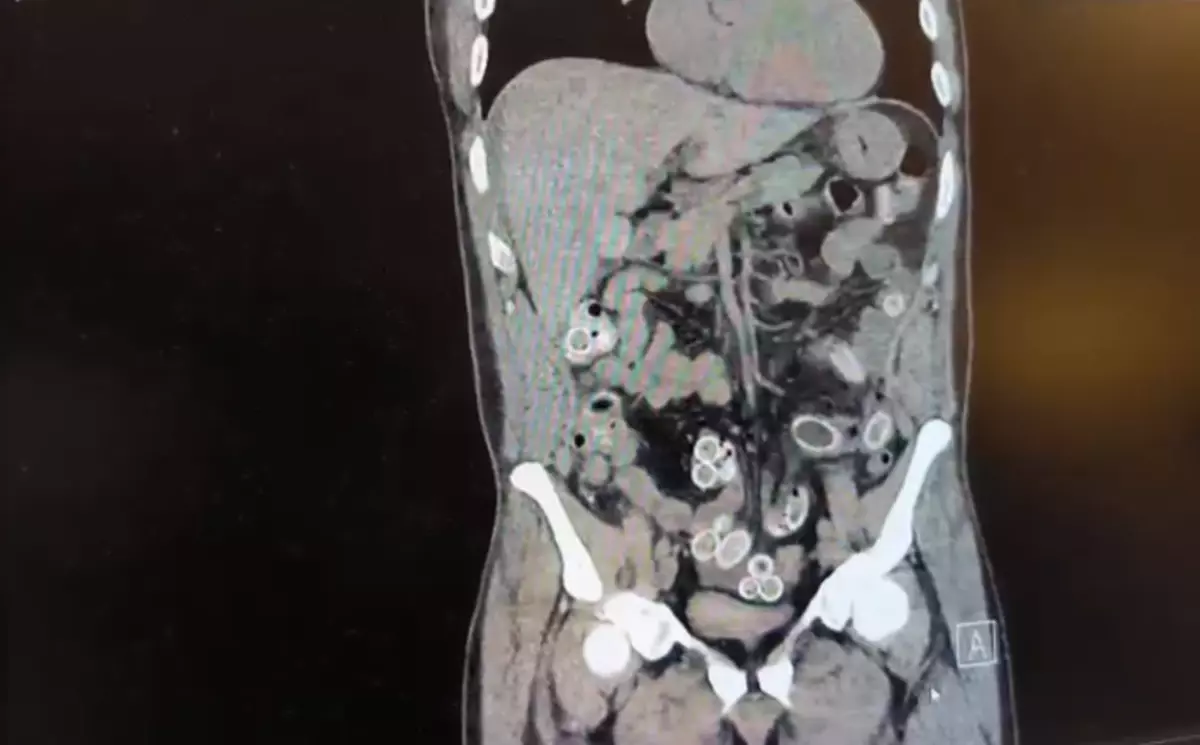

Fas'tan Uçakla Gelen Şahsın Mide ve Bağırsaklarından 49 Adet Esrar Kapsülü Çıkarıldı